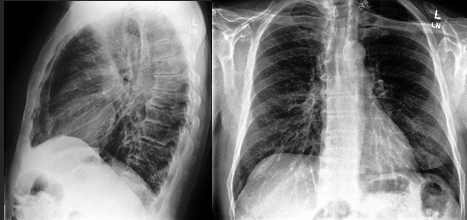

This study employs convolutional neural networks (CNNs) and the extensive CheXpert chest radiograph dataset (including more than 220,000 images) to diagnose 14 distinct chest, heart, and lung conditions from a single radiograph image. In real-world clinical settings, achieving such a comprehensive diagnosis from one x-ray scan is nearly impossible due to the high costs, lengthy diagnosis times, and inherent uncertainties. Physicians face significant challenges when diagnosing conditions solely from chest x-rays. This project aims to bridge this gap by demonstrating the feasibility and high accuracy of using CNNs for such diagnoses. The dataset comprises diverse radiograph images and associated demographic information, such as age ranges, sex, different radiograph views (frontal/lateral), ensuring broad representation. The model architecture integrates multiple layers of image analysis, including convolutional, pooling, and dense layers. The training process focused on optimizing parameters to enhance model accuracy. My deep convolutional neural network handles multivariate analysis, enabling the classification of a wide range of conditions efficiently. The model significantly reduces the diagnosis time from an average of 2 days to several weeks to around 2-3 minutes post-radiograph upload. The neural network achieved approximately 90% accuracy in diagnosing the 14 conditions, highlighting its potential for rapid and reliable clinical application. The findings suggest that neural network models can not only classify thoracic conditions from chest radiographs with high accuracy, but also offer enhanced efficiency and cost-effectiveness compared to traditional methods. This advancement represents a significant step forward in improving patient care and medical decision-making in pulmonology.

Accurately diagnosing 14 different thoracic conditions from a single chest x-ray is a complex task that traditional methods struggle to achieve due to high costs, long processing times, and diagnostic uncertainty.4 This study addresses this critical challenge by leveraging CNNs to develop a model capable of diagnosing multiple conditions with high accuracy. By addressing this gap in the existing research, the study aims to enhance diagnostic processes, reduce time and costs, and improve patient outcomes.

My deep learning model, trained on the CheXpert dataset, successfully diagnosed 14 thoracic conditions from chest radiographs with an accuracy of approximately 90%. Unlike traditional diagnostic methods that typically take 2 days to several weeks for radiological analysis and interpretation16, the model delivers results in a matter of seconds following radiograph upload. These findings highlight the capability of convolutional neural networks to perform multi-label classification tasks in complex medical imaging scenarios with both speed and precision.